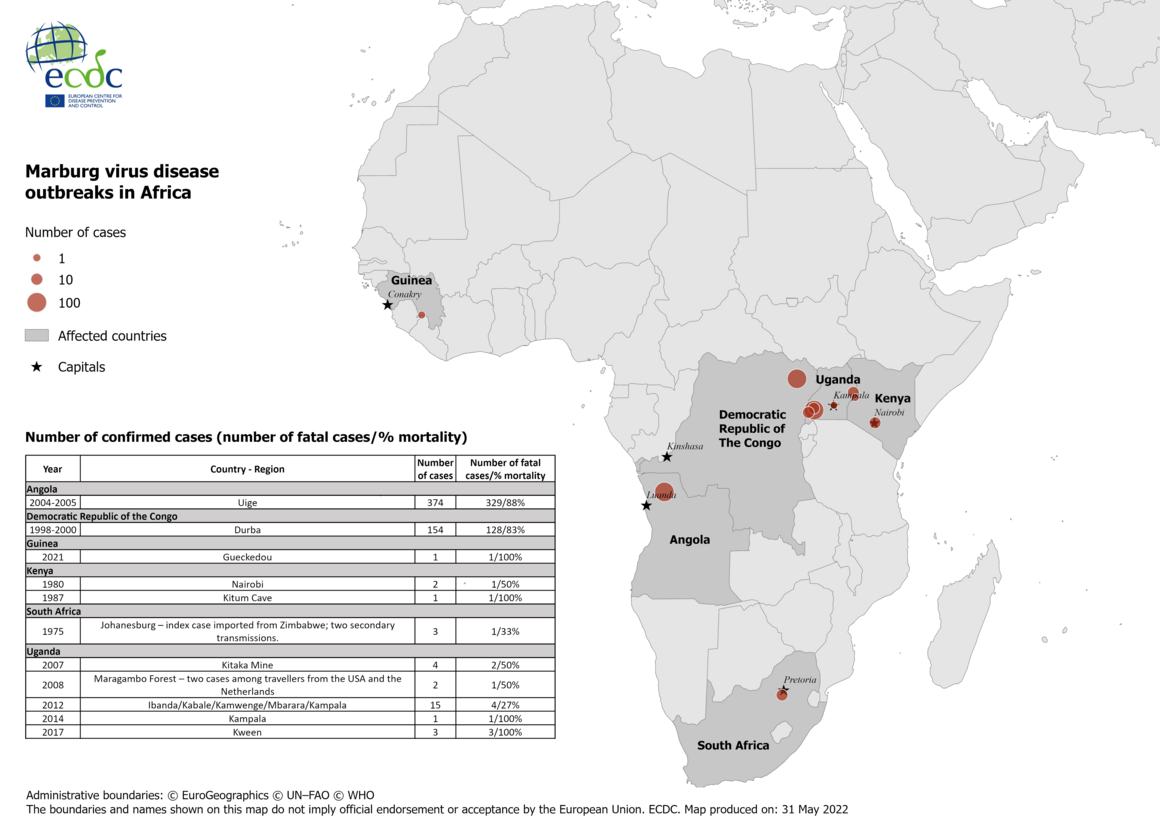

Ako se potvrdi da su dvije osobe preminule od tog virusa, to će biti drugi put da je Marburg otkriven u zapadnoj Africi nakon manjih slučajeva zaraze u Gvineji prošle godine.

Marburg virus najsmrtonosniji je virus na svijetu s obzirom na to da, prema podacima Svjetske zdravstvene organizacije, ubije i do 90 posto zaraženih. Trenutno ne postoji lijek za tu bolest.